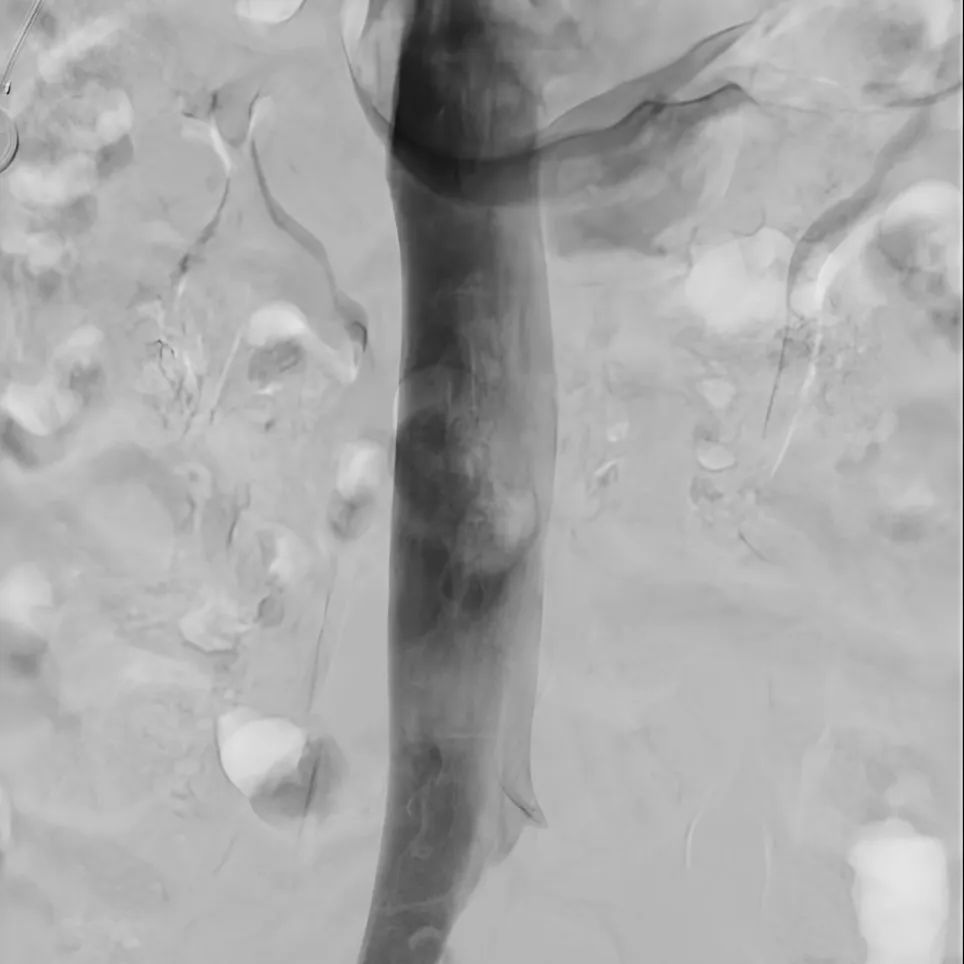

如何治療呢,可以使用血管造影X射線機(jī)(簡(jiǎn)稱(chēng):DSA),通過(guò)介入的方式治療,包括:

目前,唯邁醫(yī)療的DSA已裝機(jī)眾多三甲醫(yī)院,而剛剛完成裝機(jī)的濟(jì)南三院也在數(shù)日內(nèi)完成幾十例介入手術(shù),涵蓋經(jīng)介入造影治療,外周血管造影治療,心臟造影支架置入,滿足臨床多科室使用。

肝動(dòng)脈造影治療

神經(jīng)造影

心臟造影

支氣管動(dòng)脈造影治療

下腔靜脈+濾器